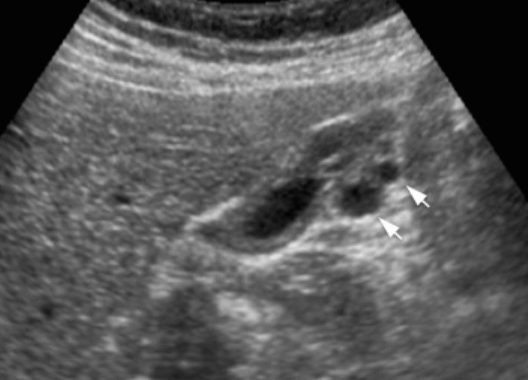

US finding

- 소낭종 (anechoic)

- 소낭종내담석에 의한 comet tail sign

- GB wall 이 두꺼워진다

담낭 선근종증 담낭 선근종증의 분류

- 분절형 (segmental type): 담낭벽이 양측에 반월상으로 비후 된다. 대칭성이 떨어지거나 불규칙적 벽비후는 악성가능성이 있으므로 제거하는 것이 좋다.

- 국소형 (fundal type): 벽비후가 저부에 국한되어 있다. 암호발부위이며 doppler 검사를 필수로 시행한다.

- 미만형 (diffuse type): 담낭벽이 광범위하게 비후 되어 있다